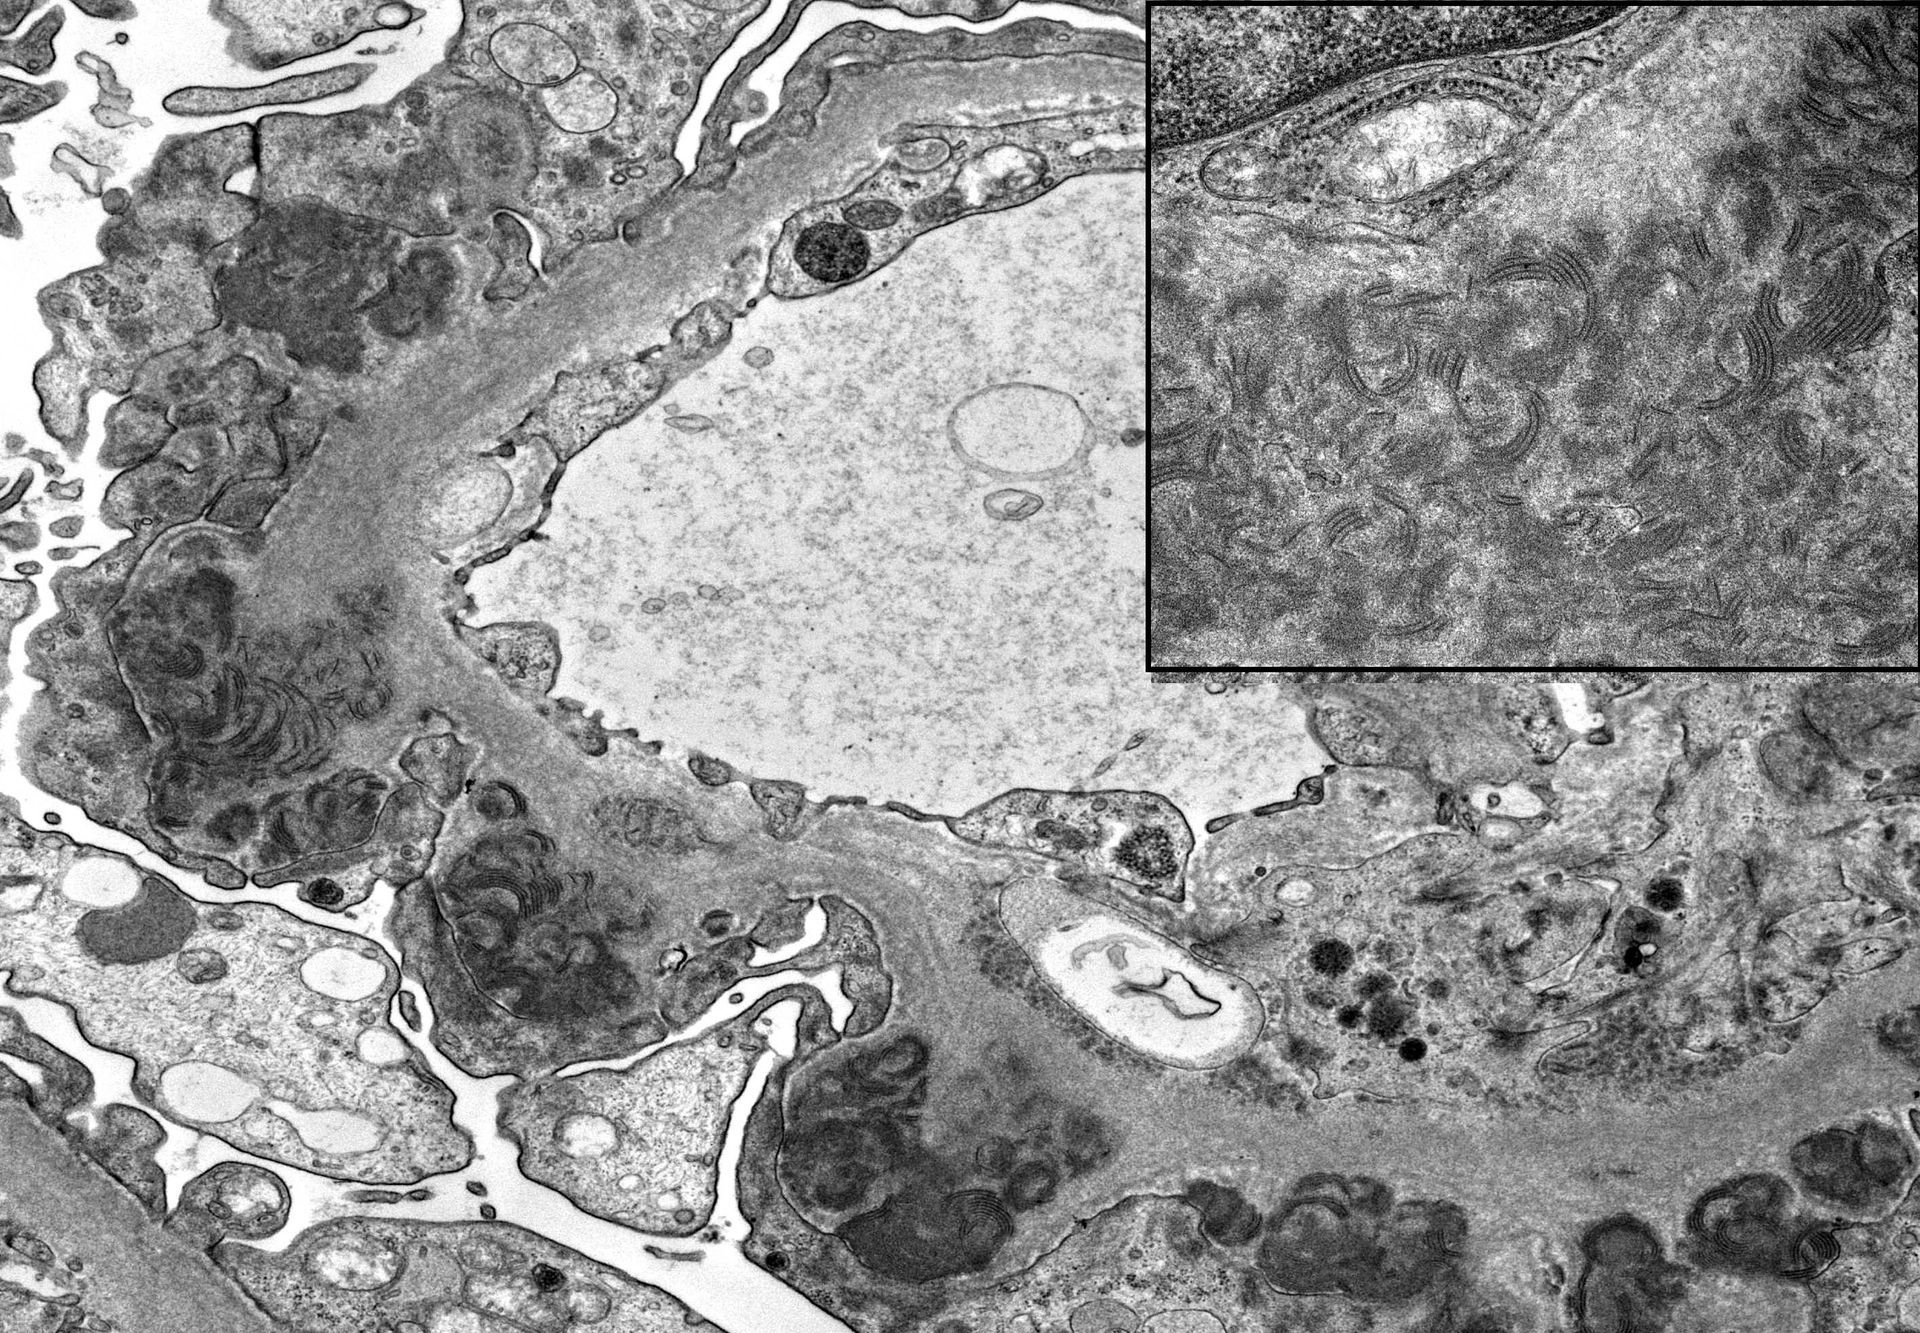

- Διαγνωστικές ημιλεπτές τομές ρητίνης